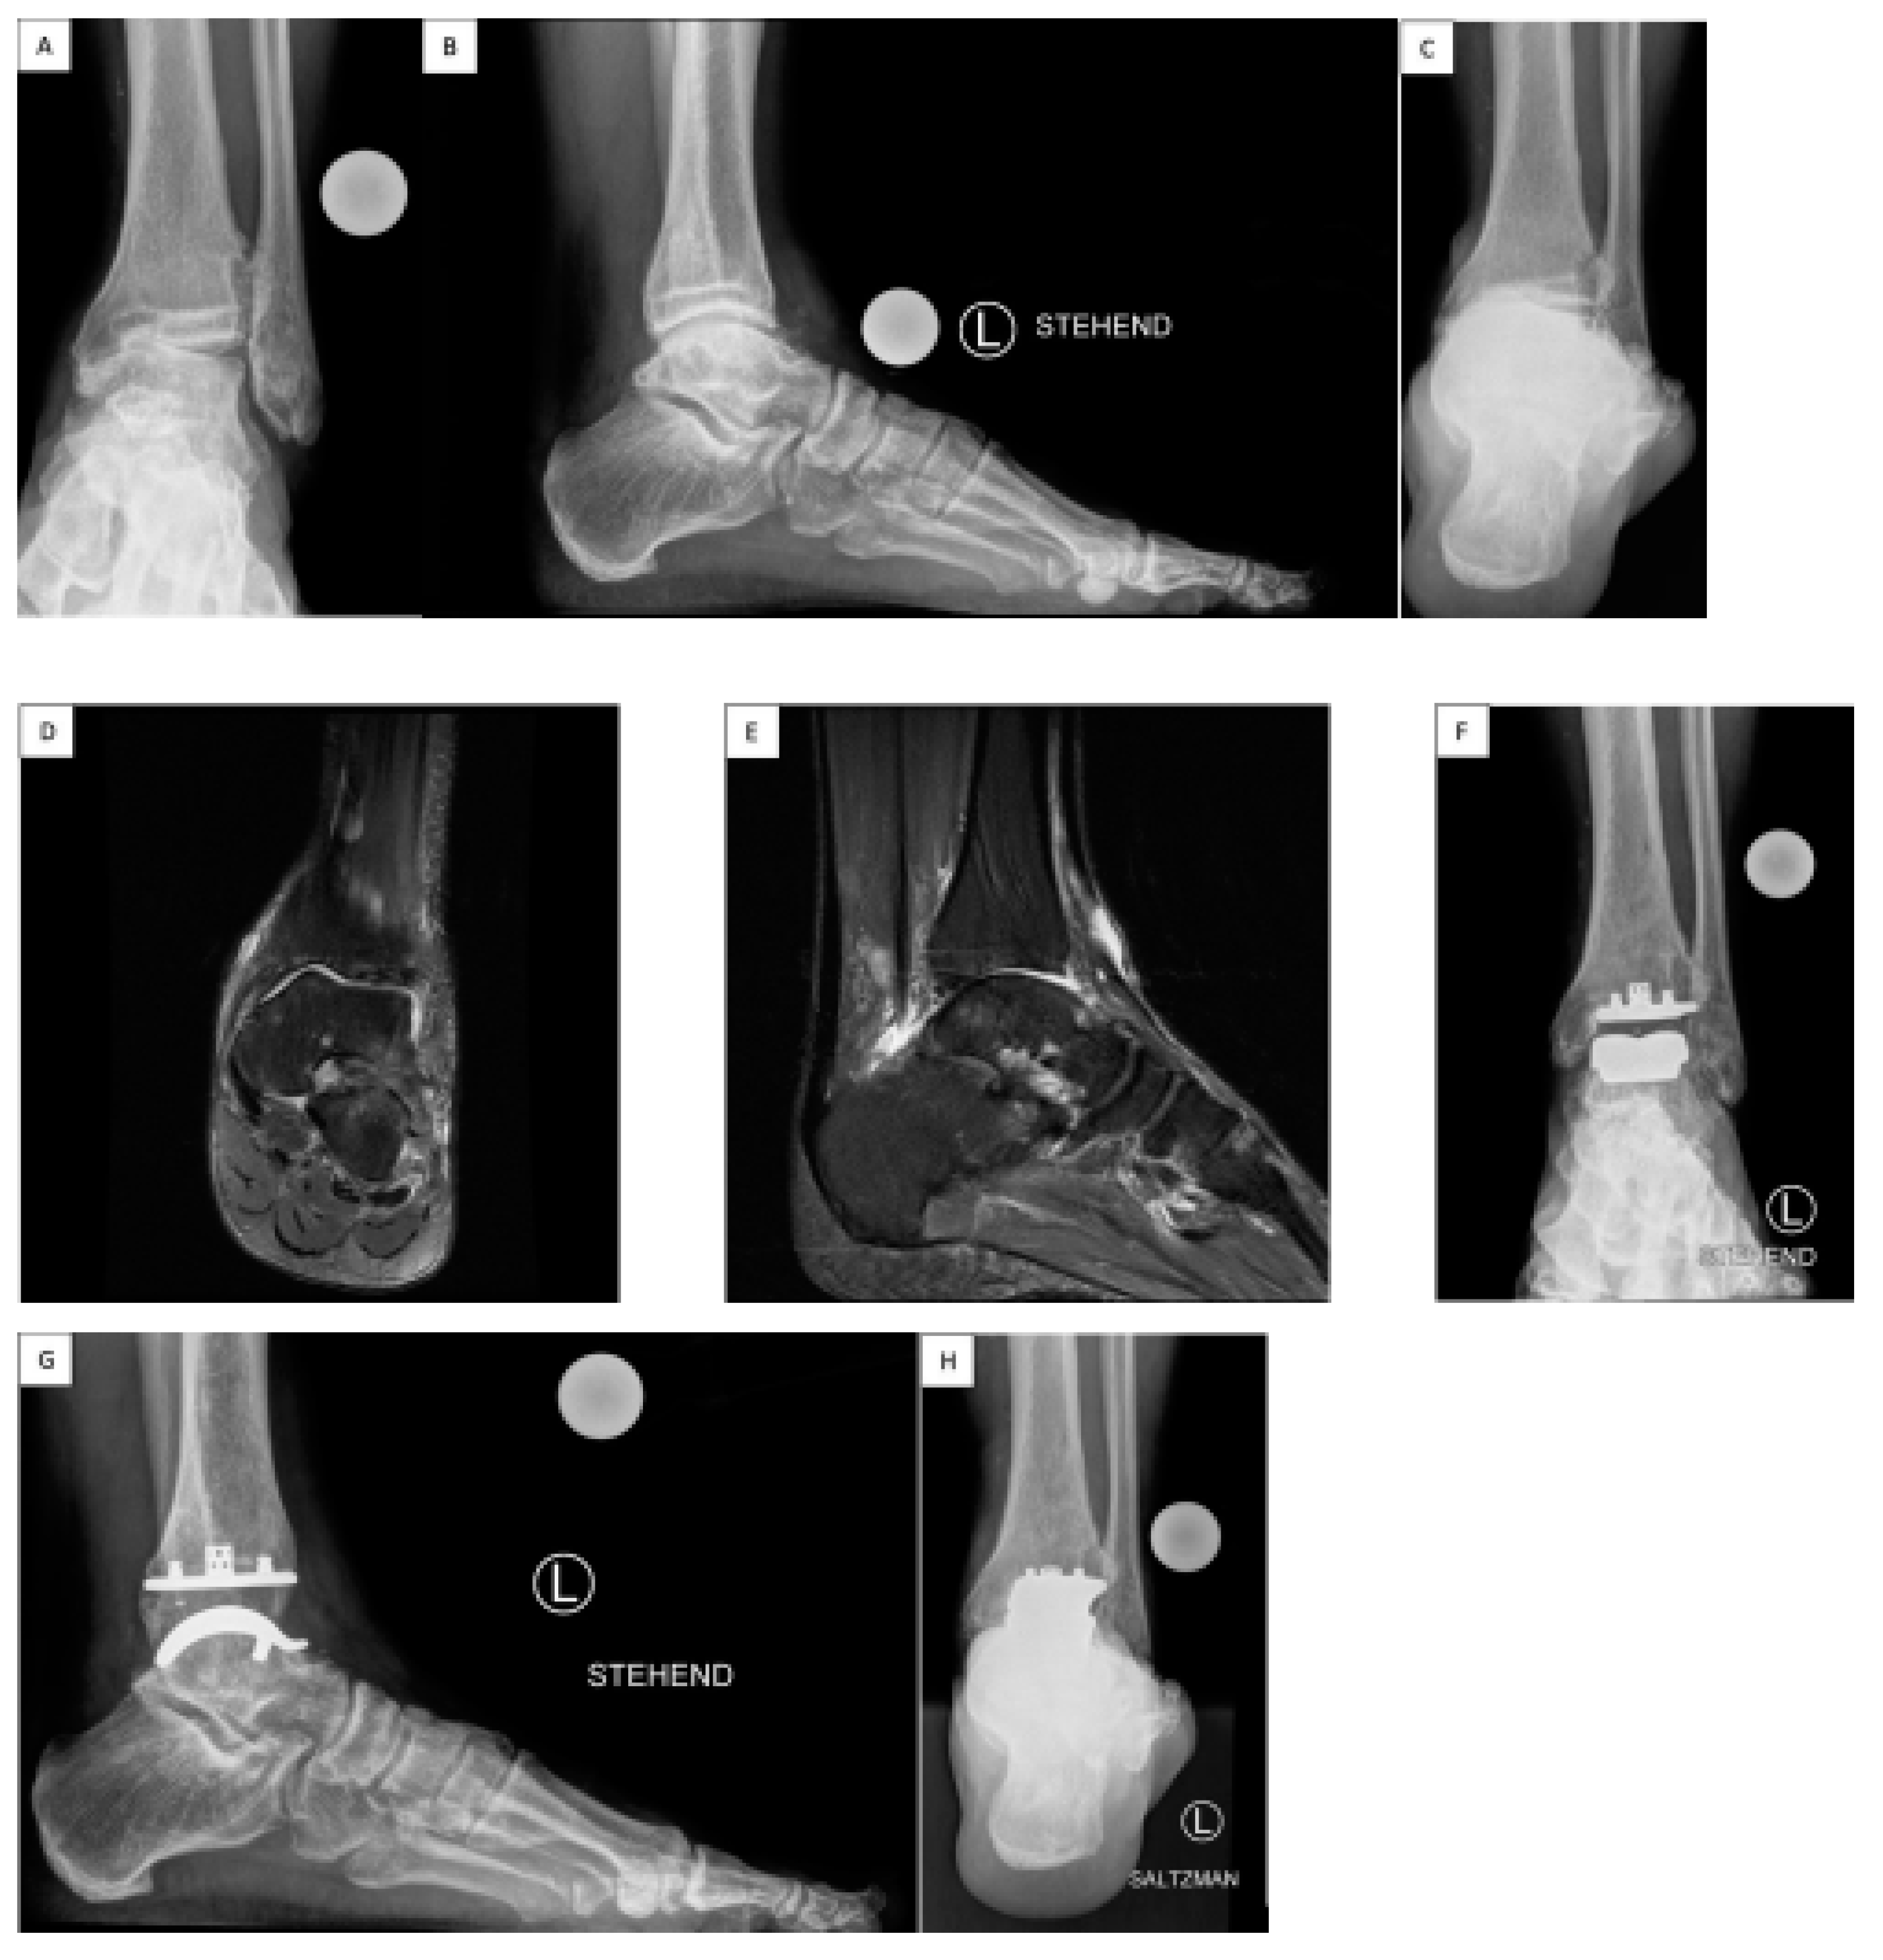

Figure 1.

Sports Active Patient with Total Ankle Arthroplasty VANTAGE Total Ankle Arthroplasty Mobile Bearing. A 59-year-old patient suffered from post-traumatic ligamentous end-stage varus ankle osteoarthritis (OA) with chronic lateral ligament ankle instability and Peroneus brevis tendon lesion (A, B, C, pre-op). The preoperative MR images show the medial predominantly ankle OA (D, E, pre-op). The surgery consisted on: TAA implantation, deltoid release, lateral ankle ligament reconstruction, and peroneus longus (PL)-to-brevis (PB) tendon transfer. After TAA surgery at recent 3 years follow-up he reached an AOFAS Ankle/Hindfoot Score of 100, VAS Pain Score 0, Dorsiflexion/Plantarflexion 25-0-40, Inversion/Eversion 30-0-10, (F, G, H), could return to a sports level of > 5h/week: hiking over 10km, skiing; and a Subjective Patients' Satisfaction Score 10 points/very satisfied. He describes a sense of the “forgotten joint” level. The radiological examination shows at 3 years follow-up a well osteointegrated TAA with no signs of lucency or loosening.